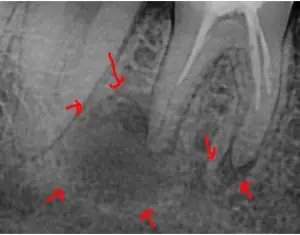

I hope you’re doing well and being safe during this unprecedented time. I wanted to share a very interesting case with you. A patient came